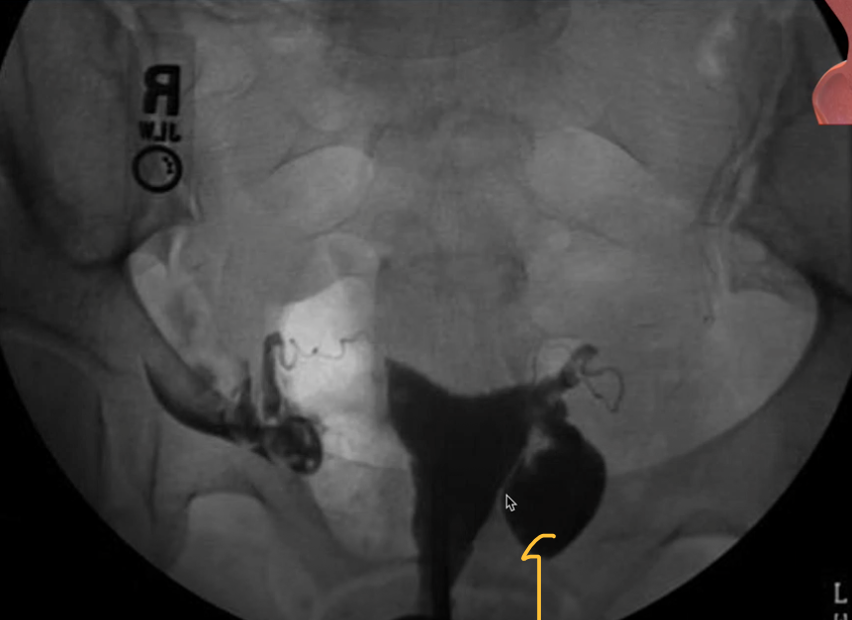

Q

What imaing modality is being used

A

Hysterosalpingogram

Commonly used for investigation of infertility/miscarriage

Assess normal shape of uterine cavity, patency of fallopian ducts, free spill of contrast into interperitoneal space

A hysterosalpingogram (HSG) isan X-ray dye test used to diagnose problems related to fertility.